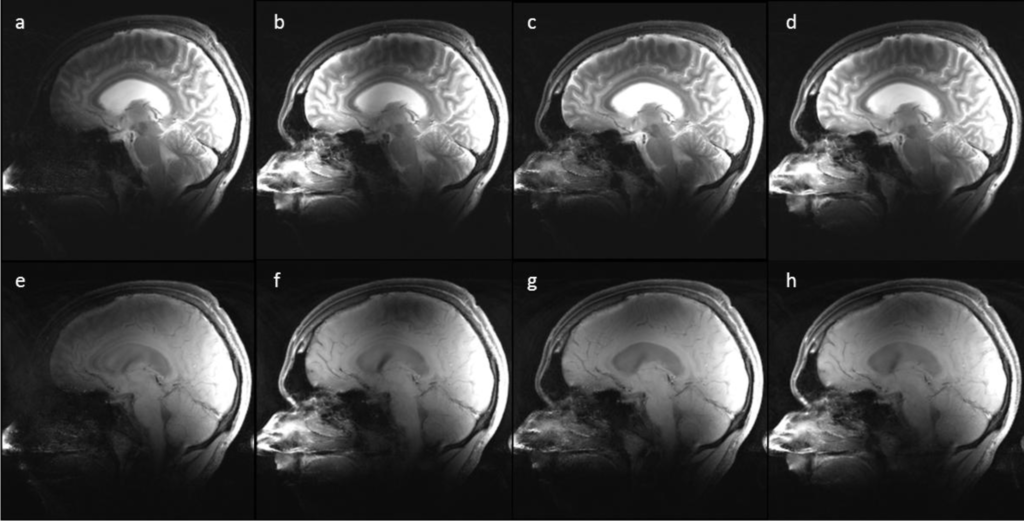

Figure 2 represents changes in the RF-power and RMMSE with slice location for all Tx channel configurations. Results with identical RF-power and identical RMMSE for all channels are represented in Figure 2a–d and 2e–h respectively. All graphs are normalized to the center slice of the 1-channel Tx global mode. For slice-selective RF shimming, each slice was shimmed individually, so the RF-power in Figure 2a changes with slice location, and for global RF shimming, the whole slice stack was shimmed so that Figure 2b depicts the same RF-power for the whole slice stack. For comparison, the RMMSE and RF-power were averaged over the entire slice stack for slice-selective and global RF shimming. The 1-channel Tx global mode has an inferior performance compared with the slice-selective RF shimming method and other Tx channel configurations, with RMMSE in B1+ being nearly 40% (RMMSE of an ideal B1+ field would be 0%), and the 1-channel Tx slice-selective mode has an RMMSE of 36%. With constant RF-power and slice-selective RF shimming, the RMMSE for 2-, 4-, and 8-channel Tx when compared with 1-channel Tx (RMMSE of 1-channel Tx scaled to 1%) was 0.82%, 0.7% and 0.56% (reduction in RMMSE was 18%, 30% and 44%) respectively, whereas with a constant RMMSE and slice-selective RF shimming, the RF-power (RF-power of 1-channel Tx scaled to 1%) for 2-, 4-, and 8-channels Tx was 0.69%, 0.51% and 0.31% (reduction in RF-power was 31%, 49% and 69%) respectively, compared with 1-channel Tx. In this scenario, the performance of global RF shimming was inferior compared with the slice-selective method. For identical RF-power, the RMMSE for 2-, 4-, and 8-channels Tx compared to 1-channel Tx was 0.94%, 0.86% and 0.76% (reduction in RMMSE was 6%, 14% and 24%) respectively and the RF-power for identical RMMSE for 2-, 4-, and 8-channels Tx compared with 1-channel Tx excitation was 0.84%, 0.59% and 0.38% (reduction in RF-power was 16%, 41% and 62%) respectively. The slice-selective RF shimming method with 8-channel Tx showed marked improvements over global RF shimming and fewer Tx channels.

Figure 4 depicts representative slices from the T2w c and the T1w SE image series, acquired with the 1-, 2-, 4-, and 8-channel Tx static shim solutions with identical RF-power. The intensity variations resemble the spatial patterns in the measured B1+ maps (Figure 3a–d). For the T1w and T2w images, the perceived image homogeneity increases with increasing number of channels for the given brain anatomy. These images were not corrected for received coil sensitivities.